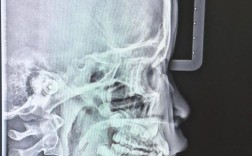

影像学检查

影像学检查是临床诊断的重要补充,尤其对于隐蔽部位龋(如邻面龋、隐匿龋)、根面龋及深龋的诊断具有重要意义,可显示肉眼无法观察的牙体硬组织破坏范围和程度。

牙片是临床最常用的影像学检查方法,包括根尖片、咬合翼片及咬合片等,根尖片可清晰显示单颗牙齿的牙冠、牙根及根尖周骨质情况,适用于检测邻面龋、牙颈部龋、继发龋及根尖周病变,邻面龋在根尖片上表现为低密度暗影,边界清晰,釉质破坏后可见牙本质透射影;深龋近髓时可见髓腔角变钝或髓室底模糊,咬合翼片(即翼片)用于检查邻面龋,尤其是上颌前牙和下颌磨牙的邻面,可减少影像重叠,提高诊断准确性,咬合片则适用于全口牙列的检查,但分辨率较低,常作为辅助手段。

曲面体层片(全景片)

曲面体层片可一次性显示全口牙齿、牙槽骨、颌骨及周围结构,适用于大面积龋病筛查、儿童龋病评估及多牙龋坏的诊断,但其分辨率较低,对细小龋坏(如早期釉质龋)显示不清,且存在影像重叠问题,需结合牙片进一步检查。

锥形束CT(CBCT)

CBCT是近年来发展起来的三维影像技术,可重建牙齿及颌骨的三维图像,分辨率高,无影像重叠,适用于复杂龋病的诊断,如邻面深龋、隐匿龋、根管治疗后再发龋及颌骨内埋伏牙伴龋等,CBCT可精确测量龋坏深度、范围及与牙髓腔的距离,为治疗方案的制定提供详细数据,但由于辐射剂量高于牙片,需严格掌握适应证。